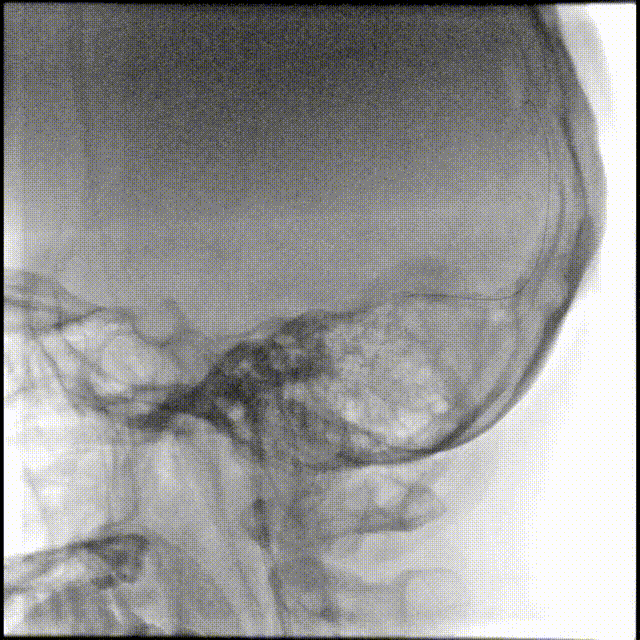

术前CTA/CTP检查,动脉成像未见明显异常,平扫CT可见右侧横窦区域高密度、左侧顶叶片状高密度,窦汇区域、上矢状窦区域高密度充盈。随后紧急性头颅MRV检查,MRV提示上矢状窦及右侧横窦区域不显影。

图注1:1A/1B 平扫CT可见右侧横窦、窦汇区域高密度,额顶叶片状高密度灶

1C 通路CTA检查动脉像未见特殊

1D/1E MRV冠状位及侧位可见上矢状窦及右侧横窦消失,左侧横窦乙状窦部分显影